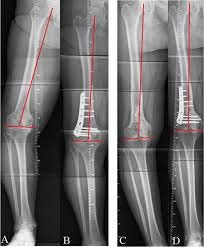

High tibial osteotomy (HTO) is a surgical procedure that realigns the knee joint by cutting and repositioning the tibia (shin bone). The procedure is often used to treat medial knee arthrosis, which can cause a bowlegged alignment that puts too much stress on the knee's inner compartment. HTO can also be used to correct varus or valgus alignment, knee instability, post-traumatic arthritis, and knee pain.

During the procedure, a wedge of bone graft or synthetic bone is placed on the medial side of the tibia and secured with screws and a plate, or a wedge of bone is removed from the outer side. HTO is usually recommended as a last resort after other non-surgical treatments have been tried.

A distal femoral osteotomy (DFO) is a surgical procedure that involves cutting and straightening the femur (thigh bone) to correct knee alignment. The goal of the procedure is to realign the knee so that the weight-bearing axis passes through the center of the knee or slightly into the inside compartment. This can help prevent excessive loading and degeneration of one side of the knee joint.

DFO is often used to treat patients with knock knees, also known as valgus knees, where the knee's mechanical axis passes laterally of the knee joint center. It can also be used to treat patients with arthritis on the outside of the knee.

There are two types of DFO: Medial closing osteotomy (MCDFO) and Lateral opening distal femoral valgus osteotomy (LODFO).

The procedure involves creating a surgical fracture at the end of the femur and repositioning the bones so they are secured in the proper alignment. After the procedure, patients typically spend at least one night in the hospital and wear a range of motion brace for at least two months while the bone heals. They may also be prescribed antibiotics for at least six days and blood thinners, and they may only be allowed to partially bear weight for two months.